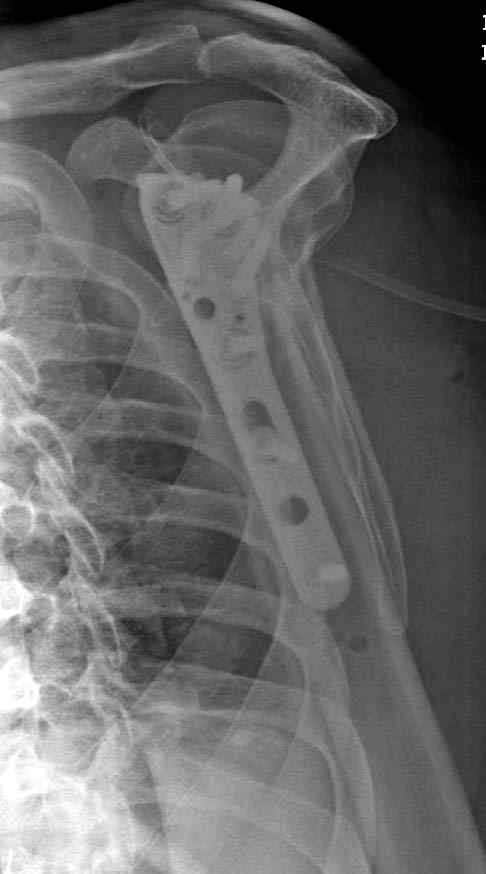

Здесь пример открытой репозиции 57 летнего с переломом плеча (1,2) смещение обнаружено на интероперационном снимке. При нормальной прямой проекция (3) угловое смещение обнаружили в аксиальной проекции (4)

После устранения смещения пластина установлена выше (5,6,7) и финальные снимки (8,9,10)